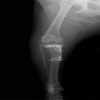

術前写真

手術前後のTPA(脛骨高平部の角度)を測定しています。

約29°から約10°へ矯正されています。

本症例は、走った後に左後肢を挙上していることを主訴に来院されました。触診時に左膝関節のクリック音を聴取、レントゲン検査にて左脛骨の前方変位が認められました。術中に、前十字靱帯の断裂及び内側半月板の損傷、内側の軟部組織の顕著な腫脹を確認。半月板切除、TPLOを実施しました。周囲組織への炎症の波及もあったため回復に時間を要しておりますが、徐々に跛行頻度は減少傾向にあり、現在も経過観察中です。術前に約29°あったTPAは術後に約10°まで矯正されました。